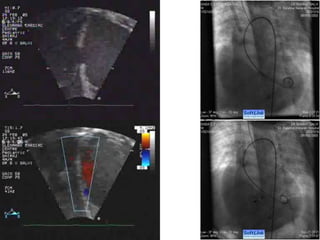

Perimembranous VSD



Device selection

 Type of the device

 Size of the device

Determinants of the Device type

 Size of the defect

 Morphology of the defect

Size of the defect

 ADO II : upto 5.5 mm

 Nit Occlud Le VSD coil : upto 8 mm

 ADO I : upto 12 mm

 AAPMVSDO & AMVSD occluder : upto 16 mm

 Modified Membranous VSD occluders

(Lifetech and Shanghai Steel Corp) : upto 19

mm

Morphology of the defect

 Presence of TV aneurysm

 Separation of the defect from the AoV

 Presence of aortic valve prolapse

 Extension into the inlet

Presence of TV aneurysm

 Mandatory for ADO I and Nit Occlud coil

 Absence of aneurysm : Need a double disc

design (Symmetrical or asymetrical)